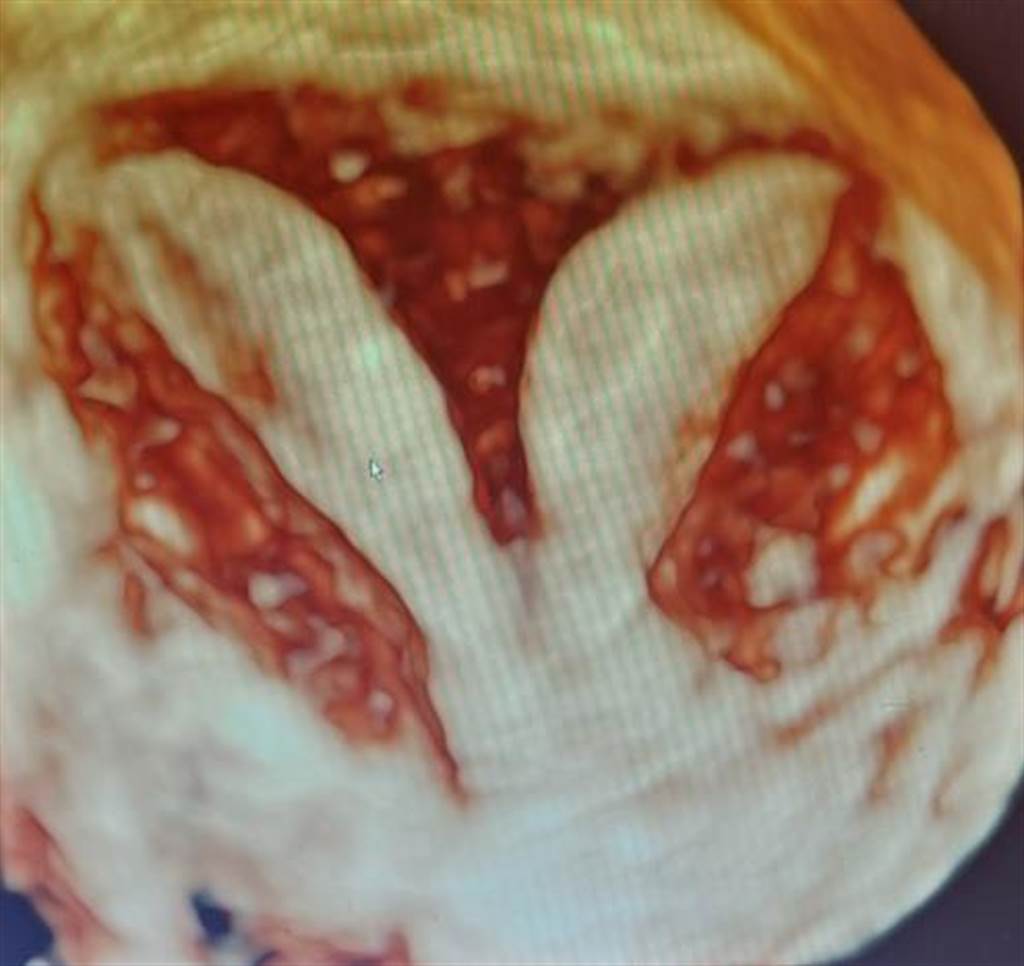

茂盛醫院副院長陳忠義指出,正常婦女只有一個子宮、一個陰道,但這名陳小姐卻有雙子宮及雙陰道,其實這屬於子宮畸形樣態中的其中一種,發生原因可追溯至胚胎在發育生殖系統時,腹腔兩側的中腎管在合而為一的過程中出現問題,於是造成子宮與陰道的先天結構異常,常見的型態還有雙角子宮、單角子宮、子宮中隔…等。

常見的型態還有雙角子宮、單角子宮、子宮中隔…等。(茂盛醫院提供/馮惠宜台中傳真)